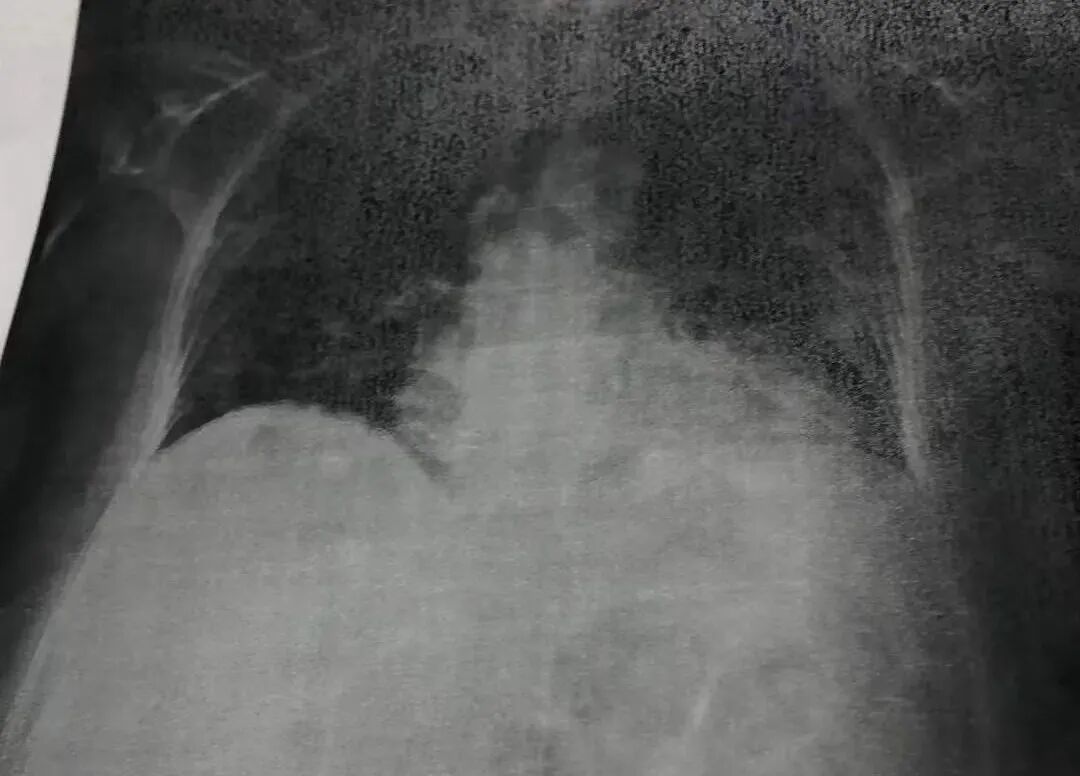

那一天我们就是密切观察血氧,基本就是坐着不动,血氧可以保持90, 上个洗手间就会掉到79。我跟群里的医生们反映后,他们担心血氧到这么低,可能已经有肺栓塞了,要我一定要去医院做全面检查:X-Ray、验血检查D-Dimer(太高的话可能已有CT查不到的小血栓)、CT。他们跟我说到医院做完检查,尽量早出院,出院时一定要带氧气瓶回家(他们已经知道医院会怎么治我,我从心底里却对医院抱有幻想,以为我去医院会得到应有的救治)。于是,当我的血氧又一次掉到80以下时,老公又打了911,救护车把我送急诊,X-ray显示肺全白,肺炎。D-Dimer 指标是上限的两倍,CT 没有血栓。急诊医生很和善地来看我,说我是COVID肺炎,需要住到COVID-19病房,会建议用抗生素 。然后我就被转到COVID-19病房了。

X-ray显示肺全白,肺炎